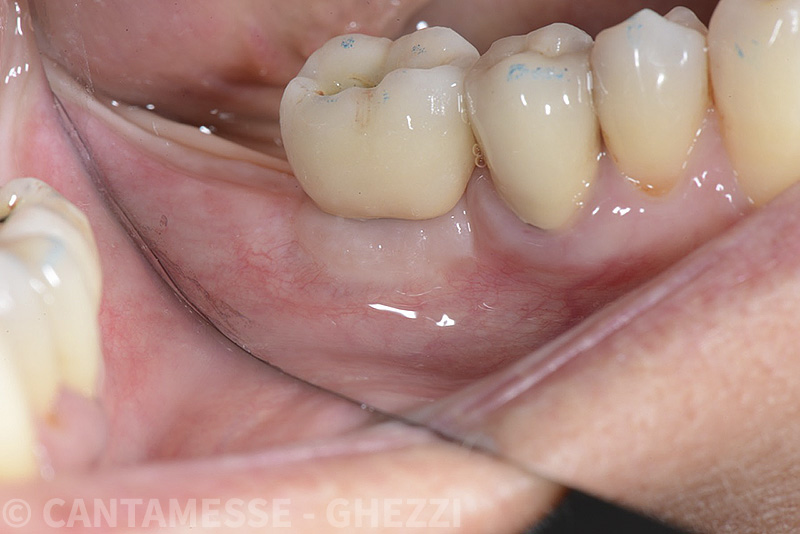

Vengono utilizzati 2 tipi di provvisori: il primo, cementato ai denti vicini, viene utilizzato dal momento dell’estrazione del dente fino ad impianto osteointegrato (circa 6 mesi); il secondo, avvitato direttamente all’impianto, ha una funzione di prova estetica ma soprattutto di guida per la maturazione dei tessuti gengivali peri-implantari portandoli verso la maturazione completa prima di posizionare la corona finale in disilicato di litio.